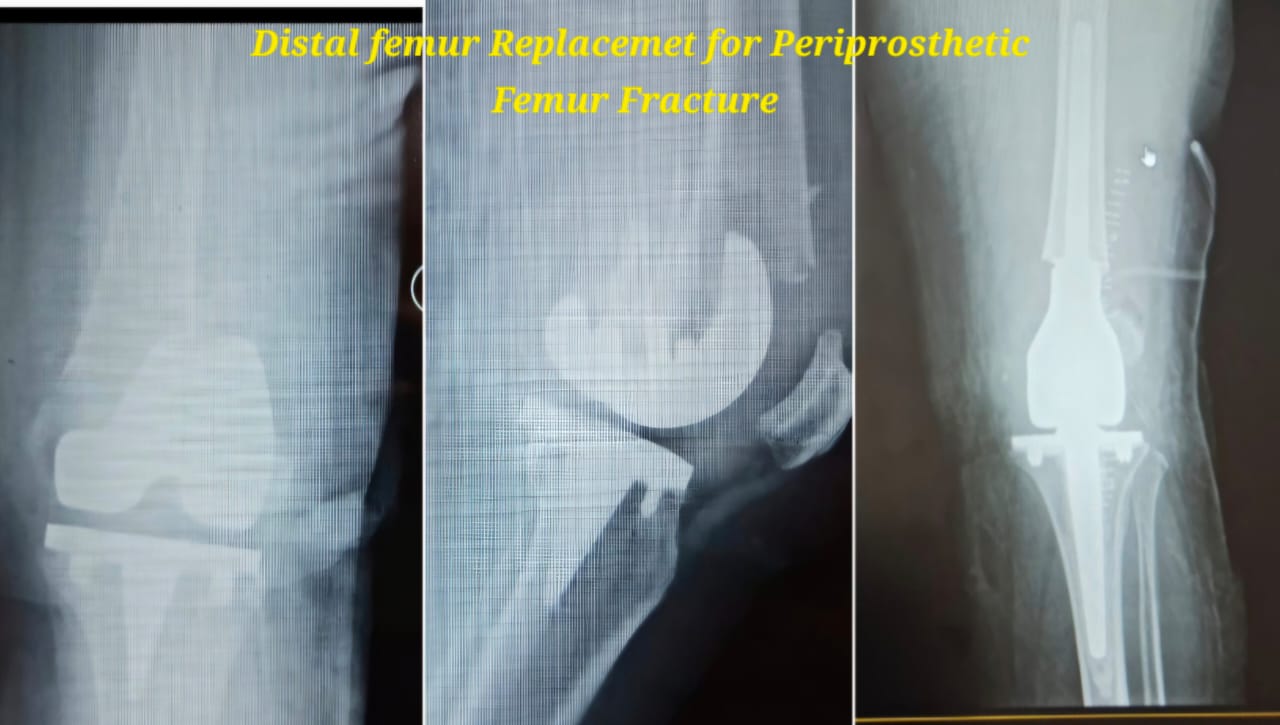

Knee replacement, also known as knee arthroplasty, is a surgical procedure performed to relieve chronic knee pain and restore joint function in patients suffering from advanced arthritis, severe joint damage, or deformities. The procedure involves replacing damaged cartilage and bone surfaces with durable artificial implants that restore smooth knee movement.

Knee arthroplasty is carefully planned based on the patient’s age, activity level, degree of joint damage, and overall health. Modern surgical techniques and advanced implant designs allow improved alignment, stability, and long-lasting outcomes with reduced postoperative discomfort.